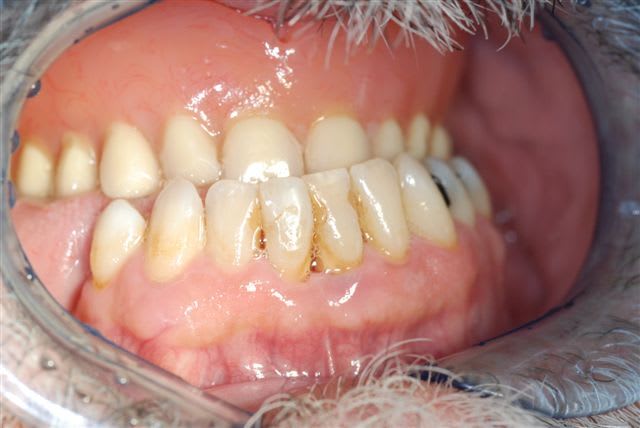

pour la mandibule: assainissement parodontal (les 41 31 ne sont pas mobiles actuellement). La résorption osseuse est importante horizontalement et verticalement, on aurait un rapport couronne/implant très défavorable sans redonner de la hauteur à la crête. Alors comment reconstruire ici: greffes en onlay? (où prélever suffisament d'os?), ROG avec de l'os autogène et membranes gore tex renforcées titane?

pour le bas je penche pour la solution d'une ROG si possible en un temps: pose des implants dans une position idéale par rapport aux dents qu'ils vont soutenir et une ROG autour des zones ostéo-émergentes de ces implants avec os autogène recouvert par membrane gore tex renforcées titane fixée apicalement par des clous ou vis d'ostéosynthèse.